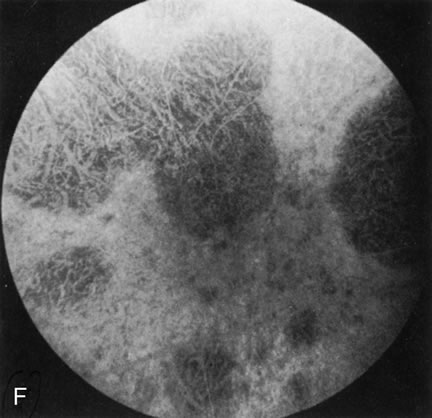

CONE DYSTROPHIES

Fluorescein angiography highlights observable fundus findings. In patients with a golden reflex the FA is normal (Fig. 2E, F) or shows a mild transmission hyperfluorescence.7